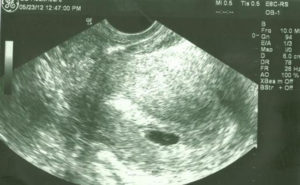

4 Weeks Pregnant Ultrasound

At this time, your growing baby is about 1mm long. This is smaller than a poppyseed, making her almost microscopic!

Even with her small size, there’s a lot going on. At this point, the fertilized egg has embedded itself in the side of your womb.